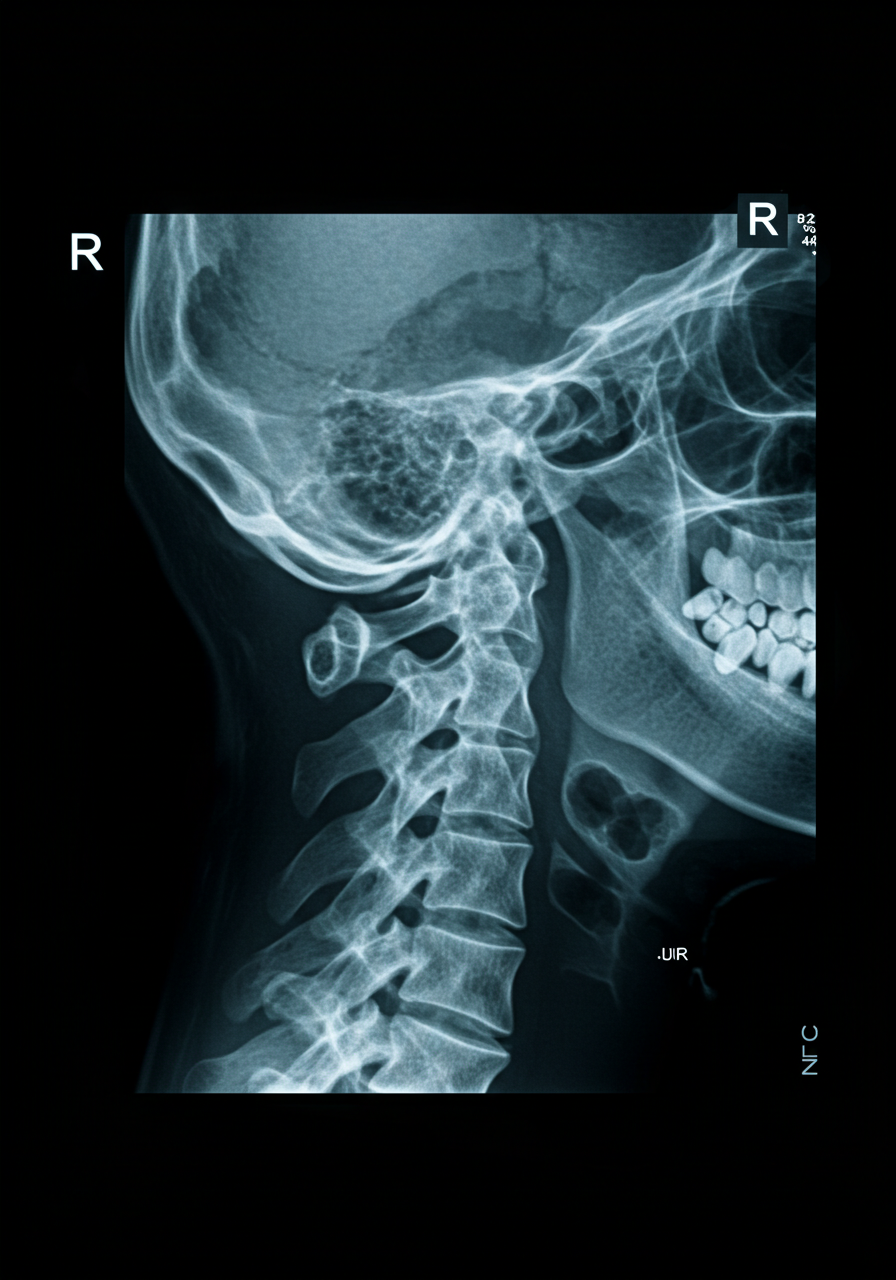

경추 디스크는 경추(목뼈) 사이에 위치한 디스크가 탈출하거나 변형되어 발생하는 질환입니다. 디스크는 척추의 충격을 흡수하는 역할을 하며, 이로 인해 통증이 유발됩니다. 주로 노화나 외상으로 인해 발생할 수 있습니다.

경추 디스크는 목뿐만 아니라 팔과 손으로 방사통이 나타날 수 있으며, 일상생활에 큰 불편을 초래할 수 있습니다. 증상이 심해지면 마비 증상이나 근력 약화가 발생할 수 있습니다.

이 질환은 정밀한 진단이 필요하며, MRI(자기공명영상) 검사를 통해 확인할 수 있습니다. 정확한 원인을 파악하는 것이 중요합니다.

경추 디스크의 주요 증상으로는 목 통증, 팔 저림, 손가락 감각 이상 등이 있습니다. 통증은 일반적으로 목에서 시작하여 팔로 퍼지는 경우가 많습니다. 이로 인해 일상생활에서 불편함을 느끼게 됩니다.